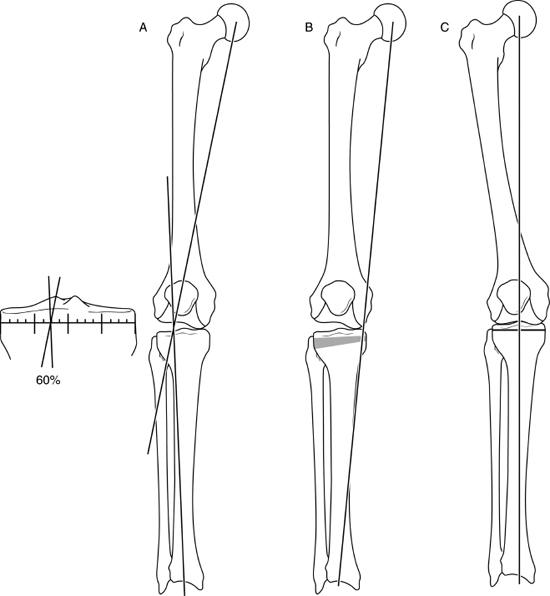

Difference between closed wedge high tibial osteotomy CWHTO a b best sale, High tibia osteotomy. a with closing wedge b with opening best sale, A closing wedge proximal tibial osteotomy. Download Scientific best sale, Knee Osteotomy Saint Luke s Health System best sale, Technique Closing Wedge The Bone School best sale, Medial closing wedge high tibial osteotomy for valgus tibial best sale, Technique Closing Wedge The Bone School best sale, Truffle Collection wide fit closed toe wedges in black ASOS best sale, Buy Women s Closed Toe Wedges Famous Footwear Australia best sale, Lateral Closing Wedge Osteotomy Musculoskeletal Key best sale, ASOS DESIGN Wide Fit Tyra closed toe wedges in natural linen ASOS best sale, Soda Black Closed Toe Wedge Heels Black heels wedges Black best sale, Closed Toe Wedge Sandals Tan Women s Shoes Monsoon Global best sale, Hitomi espadrille woven closed toe 8cm wedge heel sandals denim blue best sale, Vionic Anna Closed Toe Wedge Sandal Free Shipping Returns best sale, Tommy Hilfiger BASIC CLOSED TOE MID WEDGE Black Fast delivery best sale, Full Closed Wedge Heel Black best sale, Closed Toe Wedge Sandals Tan Women s Shoes Monsoon Global best sale, Lateral Closing Wedge Osteotomy Musculoskeletal Key best sale, Wedge Sandals Black Closed Toe Stiletto Heel PU Leather Black best sale, TUOBARR Wedge Platform Sandals Women s Closed Toe Buckle Strap best sale, ASOS DESIGN Wide Fit Treasure closed toe wedges in natural fabric best sale, Closed toe Slingback Wedge 10609 Aerosoft best sale, Madison Cleo Closed Toe Espadrille Wedge Navy Madison Heart of best sale, Wedges Sandals Shoes High Heel Hessian Cushioned Ladies Closed Toe best sale, Amazon mysoft Women s Wedge Pumps Closed Toe Low Heel Dress best sale, Cranial Tibial closing Wedge Osteotomy CTWO with patient specific surgical guides best sale, Women s Espadrille Wedge Heels Closed Toe Ankle Strap Temu best sale, Comparison between conventional and hybrid closed wedge high best sale, WHITE WEDGE HEELS Leather Heels Ankle wrap Sandals White best sale, Amazon Ruanyu Womens Platform Espadrilles Wedge Sandals Slip best sale, Froggie 10572 Closed Wedge in French Featherbys best sale, Closed Toe Wedge Sandals Tan Women s Shoes Monsoon Global best sale, Closed toe wedge sandal in beige lace by Refresh Isabel s Retro best sale, Closed Wedge Socket De Haan Special Equipment best sale, amlbb Womens Wedge Sandals Closed Toe Wedges Shoes Platform best sale, Wonders Closed Toe Wedge Sandals Silver 6703 The Shoe Horn best sale, Talitha closed Black Wedge Charming Shoes South Africa best sale, Closed Toe Wedges Shop Closed Toe Wedges Macy s best sale, Closed Toe Wedges Etsy best sale, Closed toe Slingback Wedge 10609 Aerosoft best sale, Heels Rumor Closed Toe Wedges Dorothy Perkins best sale, Franco Rossi Allison Closed Back Wedge Black Shoe Box Online best sale, Closed Wedge Sockets CWS RopeBlock best sale, Westlyn Closed Toe Wedge Sustainable Shoes Reformation best sale, Office High Heel Wedge Pumps Closed Toe Slip on Shoes for Work best sale, Lateral femoral closing wedge osteotomy in genu varum ScienceDirect best sale, Sensational Black Closed wedge Order from Rikeys faster and cheaper best sale, Lace Up Ankle Closed Toe Jute Trim Wedges Closed toe espadrilles best sale, Tibial Osteotomy with Closed Wedge best sale.

Technique Closing Wedge The Bone School

Technique Closing Wedge The Bone School

Lateral Closing Wedge Osteotomy Musculoskeletal Key